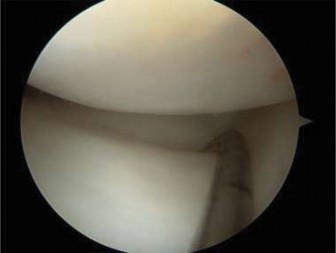

Clinical & Radiographic Imaging